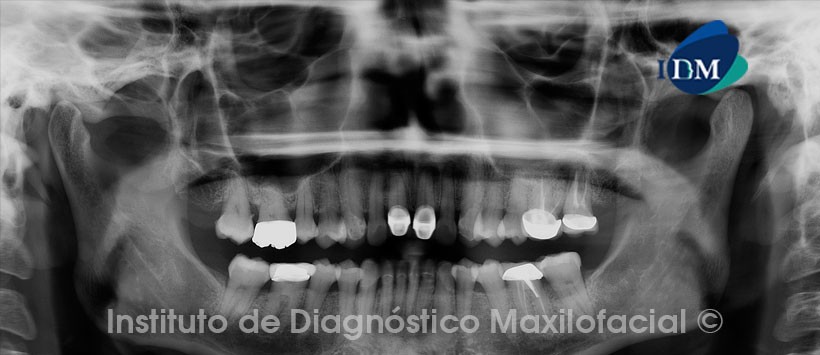

Paciente femenino, 47 años de edad es referida al Instituto de Diagnóstico Maxilofacial (IDM) para evaluación debido a que presenta leve molestias en zona maxilar superior izquierda.

A la evaluación de la radiografía panorámica se aprecia material de obturación de conductos en piezas 2.6 y 2.7 con probable proceso a nivel apical. Así mismo presenta lesión apical en piezas 1.1, 2.1, 3.2, 4.2, en relación a restauraciones coronales.(Figura 1)